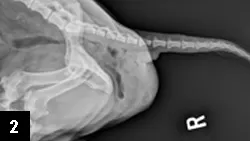

Figure 2. Caudal aspect of lateral abdomen reveals marked dilation, sacculation, and redundancy of rectal tissue at the region of herniation.

Diagnosis of perineal herniation is based on the clinical findings of perineal swelling (often reducible via external compression), and colonic dilation and lateral deviation (Figure 2.) resulting from loss of muscle support (confirmed by digital rectal examination). Unilateral cases provide asymmetry for comparison.